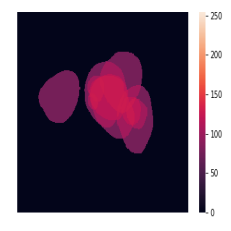

A few sample images and the corresponding masks of the polyp dataset in HyperKvasir are shown in Fig 2. The polyp images are RGB images. The masks of the polyp images are single-channel images with white () for true pixels, which represent polyp regions, and black () for false pixels, which represent clean colon or background regions. In this dataset, there are different sizes of polyps. The distribution of polyp sizes as a percentage of the full image size is presented in the histogram plot in Fig 3, and we can observe that there are more relatively small polyps compared to larger polyps. Additionally, a subset of this dataset was used to prove that the performance of segmentation models trained with small datasets can be improved using our SinGAN-Seg pipeline, and the whole dataset was used to show the effect of using SinGAN-Seg generated synthetic images instead of a large dataset which has enough data to train segmentation models. In this regard, this dataset was used for two purposes:

In total, we have generated synthetic polyp images and the corresponding masks. SinGAN-Seg generates random samples with high variations when the input scale is . This variation can be easily recognized using the standard deviation (SD) and the mean mask images presented in Fig 5. The mean and SD images were calculated by stacking the generated mask images corresponding to the synthetic images related to a real image and calculating pixel-wise std and mean. Bright color in std images and dark color in mean images mean low variance of pixels. In contrast, dark color in std and bright color in mean images reflect high variance in pixel values. By investigating Fig 5, we see that small polyp masks have high variance compared to the large polyp mask as presented in the figure.